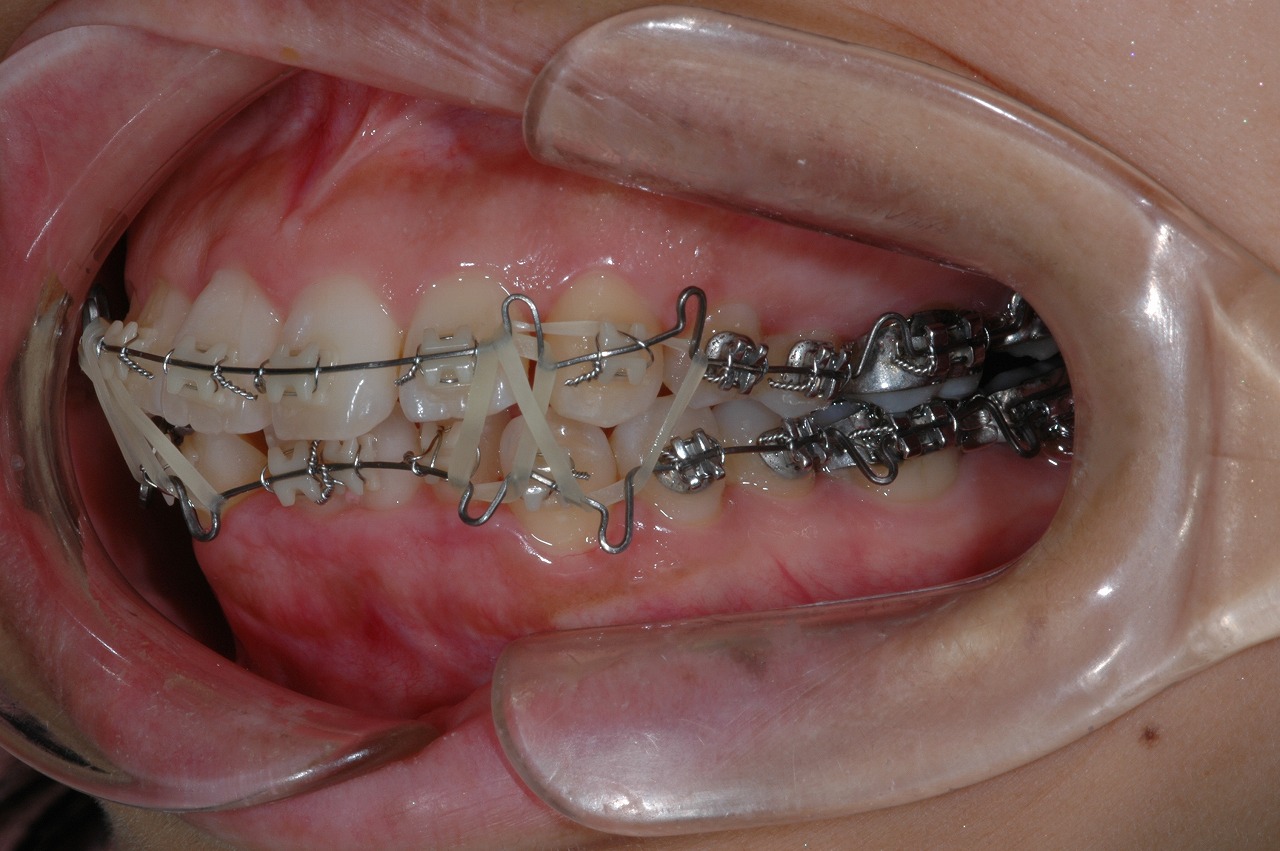

4.装置

マルチブラケット装置

1年4か月